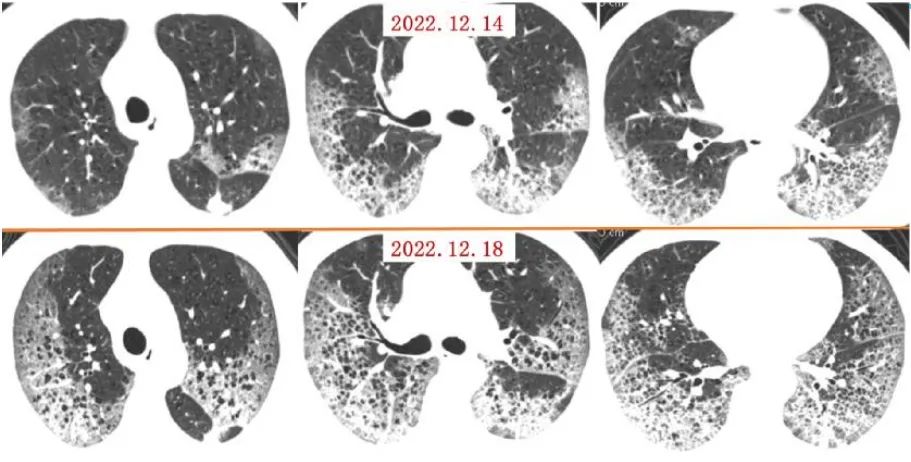

案例一,61歲,女性,確診病例

胸片顯示整個雙肺已經(jīng)白化

影像所見:有慢性阻塞性肺疾病病史。2周前受涼后出現(xiàn)發(fā)熱,伴咳嗽、咳痰。入院后給予吸氧,5天后出現(xiàn)口唇紫紺 ,改為BIPAP呼吸機輔助通氣。12月14日和12月18日,兩肺病灶自肺野外周、下后部向中心和上部迅速擴展,表現(xiàn)為“白肺”。